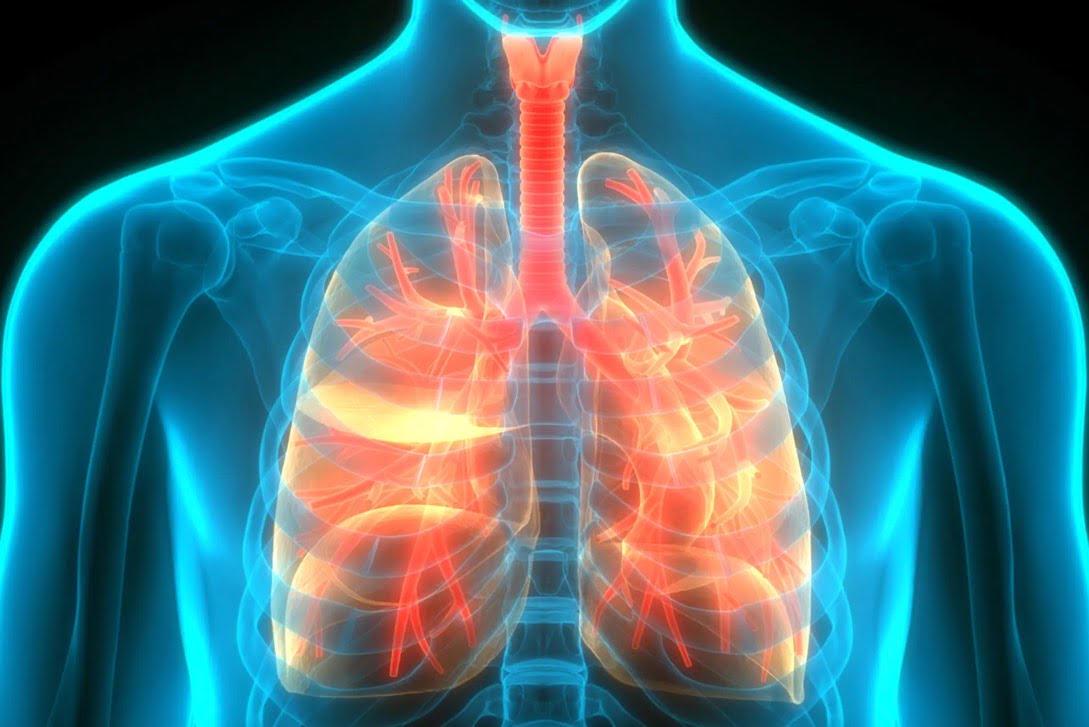

ایجاد درمانهای موثر برای بیماری های ژنتیکی ریه مانند فیبروز کیستیک دشوار است. اما ممکن است آنچنان هم که قبلا فکر میکردیم طول نکشد، زیرا دانشمندان نوع جدیدی از نانوذرهها را توسعه میدهند که میتواند فناوری ویرایش ژن را مستقیماً به ریههای موش منتقل کند.

اما محققان MIT و دانشکده پزشکی دانشگاه ماساچوست نانوذره لیپیدی جدیدی ایجاد کردهاند که ریهها را هدف قرار میدهد، جایی که میتواند mRNA را تغییر دهد.

هنگامی که ساختار نانوذرات لیپیدی موثر پیدا شد، محققان آن را روی موش آزمایش کردند. آنها دریافتند که می توانند از این نانوذرات برای انتقال mRNA کد کننده اجزای ویرایش ژن CRISPR/Cas9 به ریههای حیوانات با استفاده از روشی به نام القای داخل تراشه – وارد کردن یک ماده به طور مستقیم به نای (نای) – استفاده کنند که امکان کنترل دوز بیشتر استنشاقی را فراهم می کند.

محققان همچنین دریافتند که نانوذرات جدید به سرعت شکسته شده و ظرف چند روز از ریهها پاک می شوند و در نتیجه خطر التهاب را کاهش می دهند. توسعه آنها می تواند در آینده برای اصلاح جهش ژنتیکی که باعث فیبروز کیستیک و سایر بیماری های ژنتیکی ریه می شود مورد استفاده قرار گیرد.